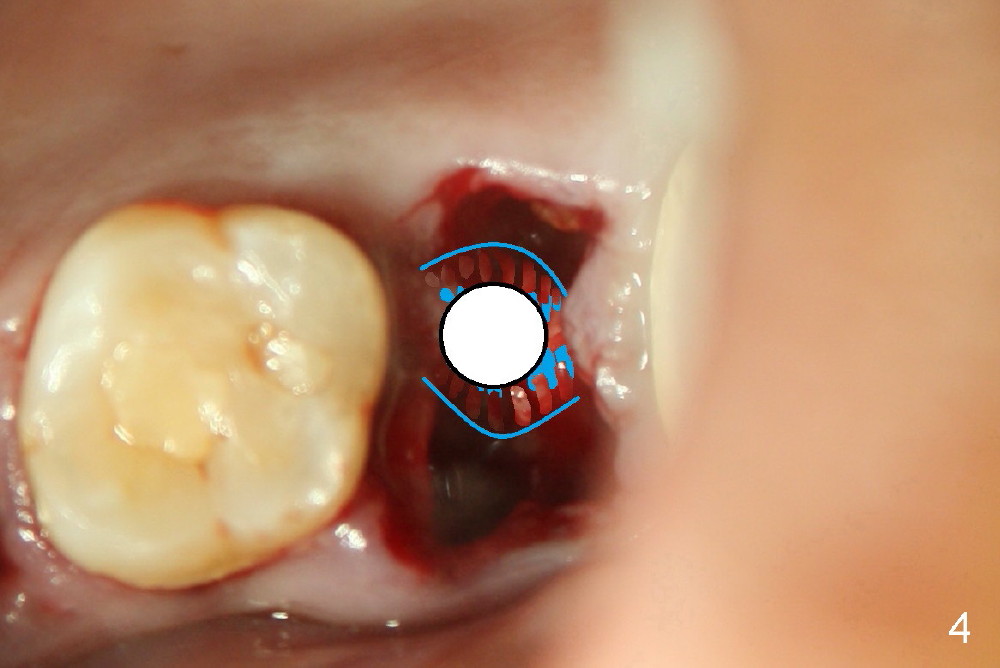

A 43-year-old lady has multiple nonsalvageable teeth. The first surgery involves two immediate implants in the upper left sextant (Fig.1: #13 and 15). The tooth #15 has 3 residual roots (MB, DB, P). There is no septum left between the first two roots when the tooth is extracted. A septum exists between the palatal (P) and buccal (B) sockets (Fig.2). Bone expansion technique is utilized to create an osteotomy in the septum. However, the smallest rounded tapered osteotome cannot be driven into the narrow septum; it slides (Fig.5). To get an initial engagement, a slot is created by high-speed surgical handpiece and fissure bur on the top of the septum. A series of blade-like osteotomes are inserted into the septum for sectioning (Fig.2 >). The smallest rounded osteotome is now easy to be inserted into the middle of the septum (Fig.3 circle, Fig.6 O). The septum is expanded by larger osteotomes (Fig.4 white circle; Fig.7 O) and tap (Fig.9 T). The septum continues being expanded when a 6x14 mm implant is placed (Fig.8,10 I). The insertion torque is more than 60 Ncm. No bone graft is placed. The palatal gap is closed by a palatal flap.